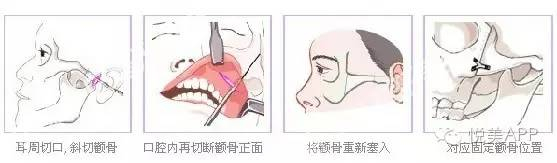

首先我们来了解一下颧骨内推的术式

总的来说颧骨手术就是:前方从口腔内切口进入,后方从耳前切口进入,剥离开截骨部分组织之后,在骨膜下方操作,截骨后固定。

口腔内切口,剥离组织

切割颧骨

耳前切口

颧骨部位L型切口,去掉部分骨头,如图示

向内推移,并前后用钛钉固定

最后呈现颧骨降低,正面脸变窄的效果